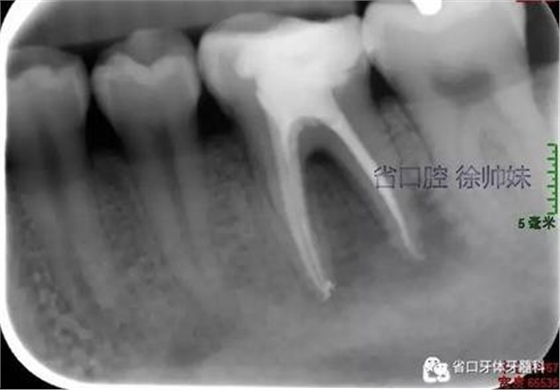

處理:36橡皮障隔濕,顯微鏡下去除封藥,沖洗根管,超聲蕩洗,熱牙膠連續(xù)波加壓充填根管(AH-PLUS),玻璃離子墊底,自酸蝕粘接,納米樹脂充填,調(diào)合,拋光。頰側(cè)牙周袋內(nèi)沖洗,置牙康。根尖片(圖3)顯示恰填,囑勿用患牙咬硬物,定期復(fù)查。

圖3 根充片